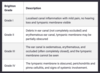

How can you risk score otitits externa?

Brighton Grading Scheme